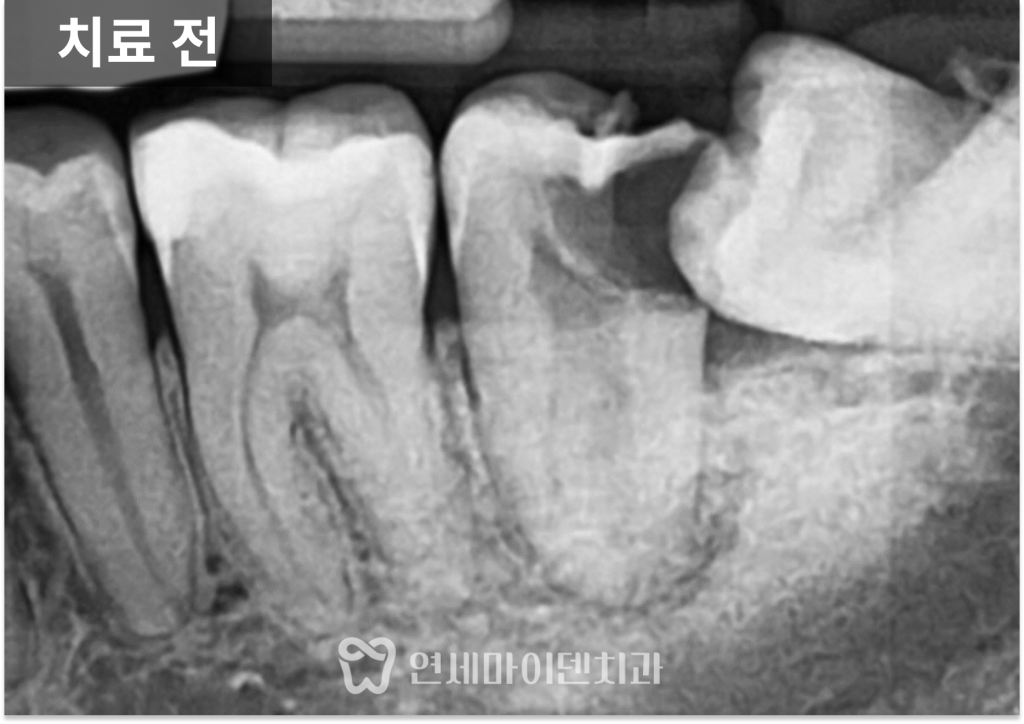

또한 해당 어금니는

뿌리 구조가 C자 형태로 연결된

해부학적으로 복잡한 형태를 가지고 있어

신경치료 난이도가 높은 조건이었습니다.

충치를 제거해보니

치아의 절반 이상이 손상된 상태였고,

잇몸이 안쪽으로 말려 들어가 있어

치료 과정 중 출혈도 많은 상황이었습니다.

그럼에도 불구하고

치아 뿌리 상태는 비교적 유지되어 있었고,

남아 있는 치질이 약 50% 정도 확인되어

보존 치료를 시도해볼 수 있는 조건이었습니다.